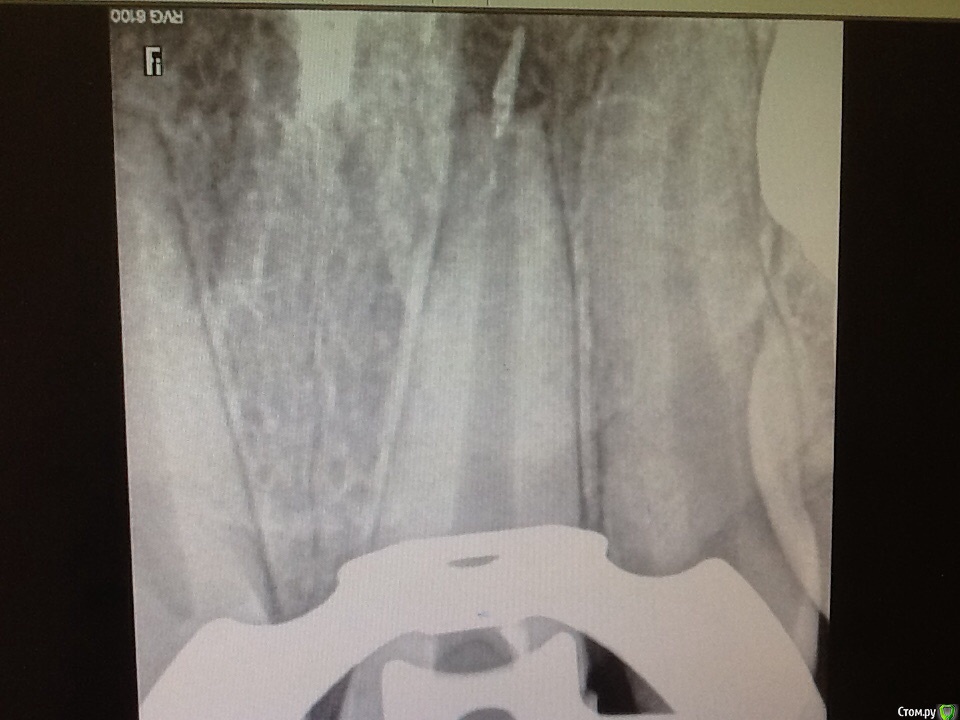

Л Ю С Я Опубликовано 29 мая, 2015 Поделиться Опубликовано 29 мая, 2015 Собственно в этом весь вопрос. Может кто то пробовал. В микроскоп вижу, апекс 70. Ретроградный путь пока не рассматривается. Ссылка на комментарий

M@estro Опубликовано 29 мая, 2015 Поделиться Опубликовано 29 мая, 2015 Резорбция, я б ретроградил. 3 Ссылка на комментарий

Kolchanov Опубликовано 29 мая, 2015 Поделиться Опубликовано 29 мая, 2015 Оставить как есть. Это не препятствие для заживления. Ссылка на комментарий